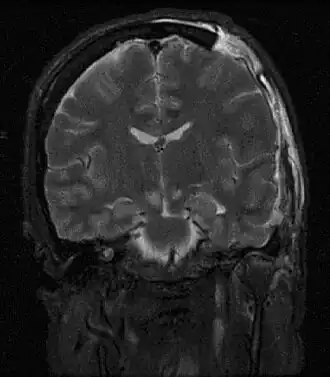

![]() Resonancia magnética mostrando lesión causada por hernia cerebral. | ||